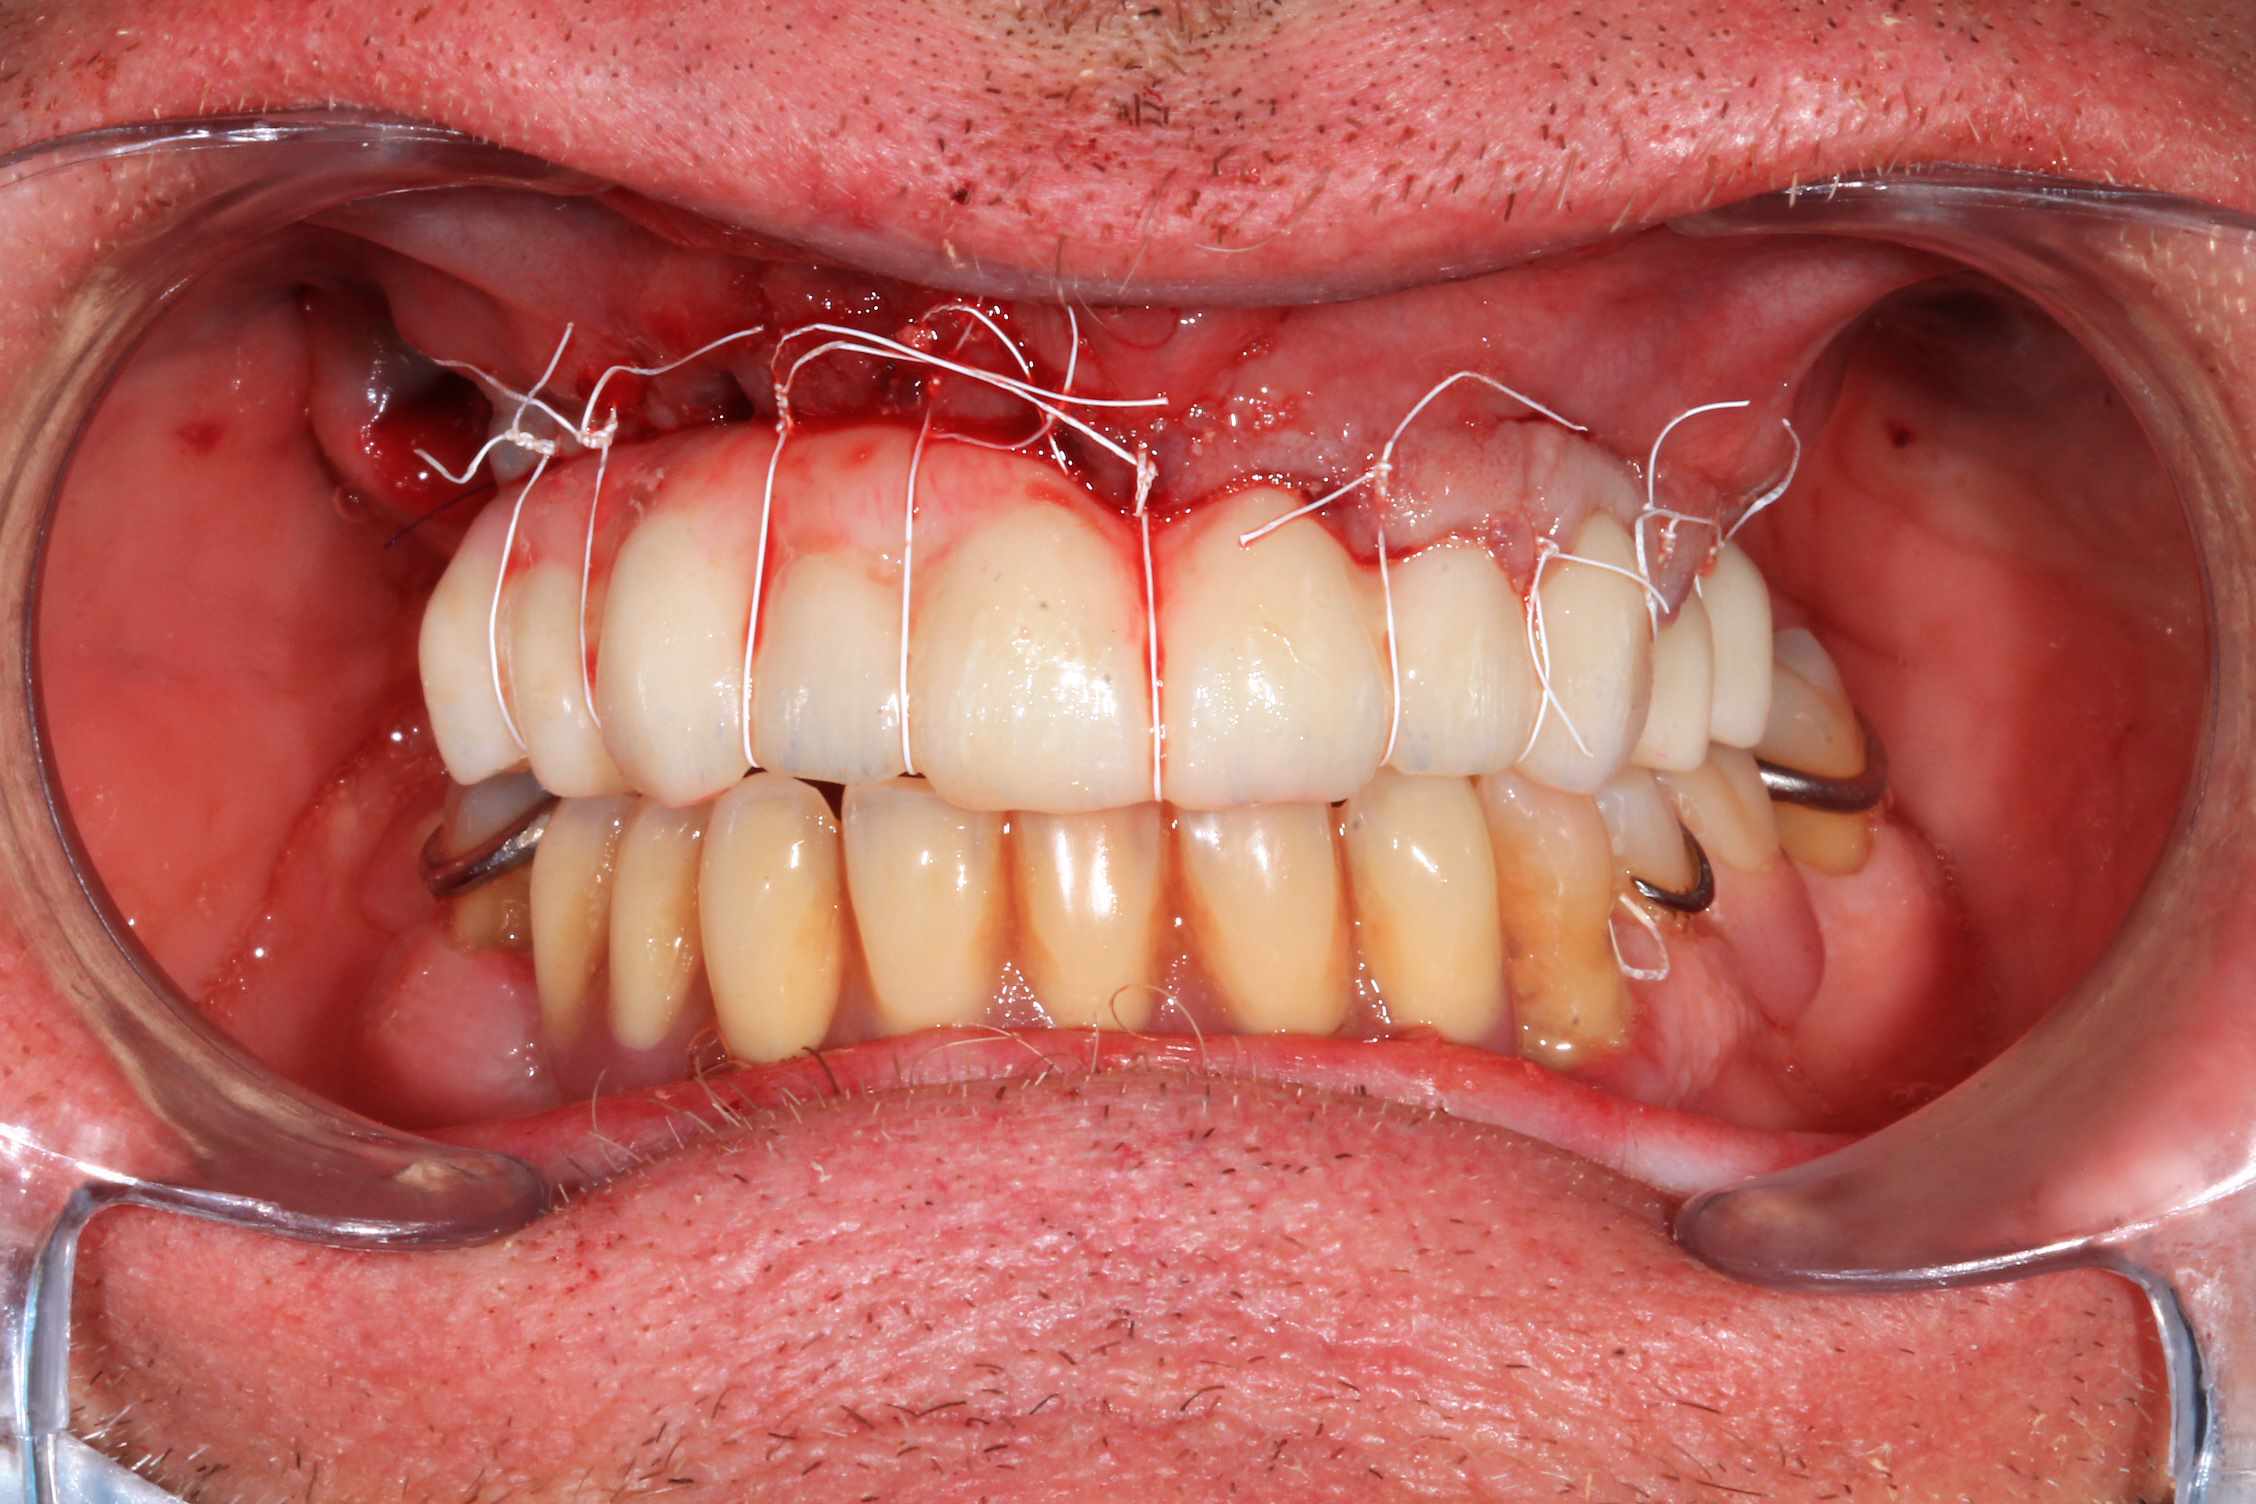

Chir : extraction, implant flapless et pose du bridge imprimé Flexera rosenscrew.

Oo2hlrfz7899rhfapzhptk1dqg77 - Eugenol

57n0uy1188a85maq093dyeqfkqlh - Eugenol

Ujfw7wykxh3fhbwxszqf740ci3rt - Eugenol

S7tplsv5ffydeo8n22bhttsnmndc - Eugenol